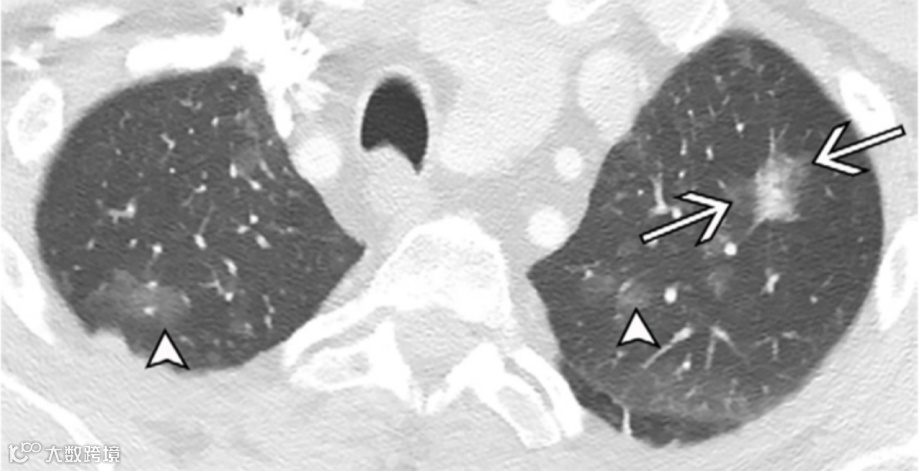

图17. 70岁男性非小细胞肺癌(NSCLC)患者的多灶性磨玻璃影或鳞状病灶(多灶性腺癌)。

左上叶的部分实性结节(箭头之间)为主病灶,其总直径为2.2厘米,其中实性成分为1.2厘米;这通常会被描述为T1b期病变。然而,在双肺中还有多个磨玻璃结节(短箭头)。对于多发磨玻璃结节或鳞状肿瘤,国际肺癌学会(IASLC)建议使用主病灶进行T分期。

由于存在多个额外的磨玻璃结节,总体描述为T1b(m),其中“m”代表多个。在计算主病灶以外的磨玻璃恶性病灶时,仅包括直径大于5mm的结节,因为直径小于5mm的结节被认为是非典型腺瘤样增生,这是肺腺癌的前驱病变。